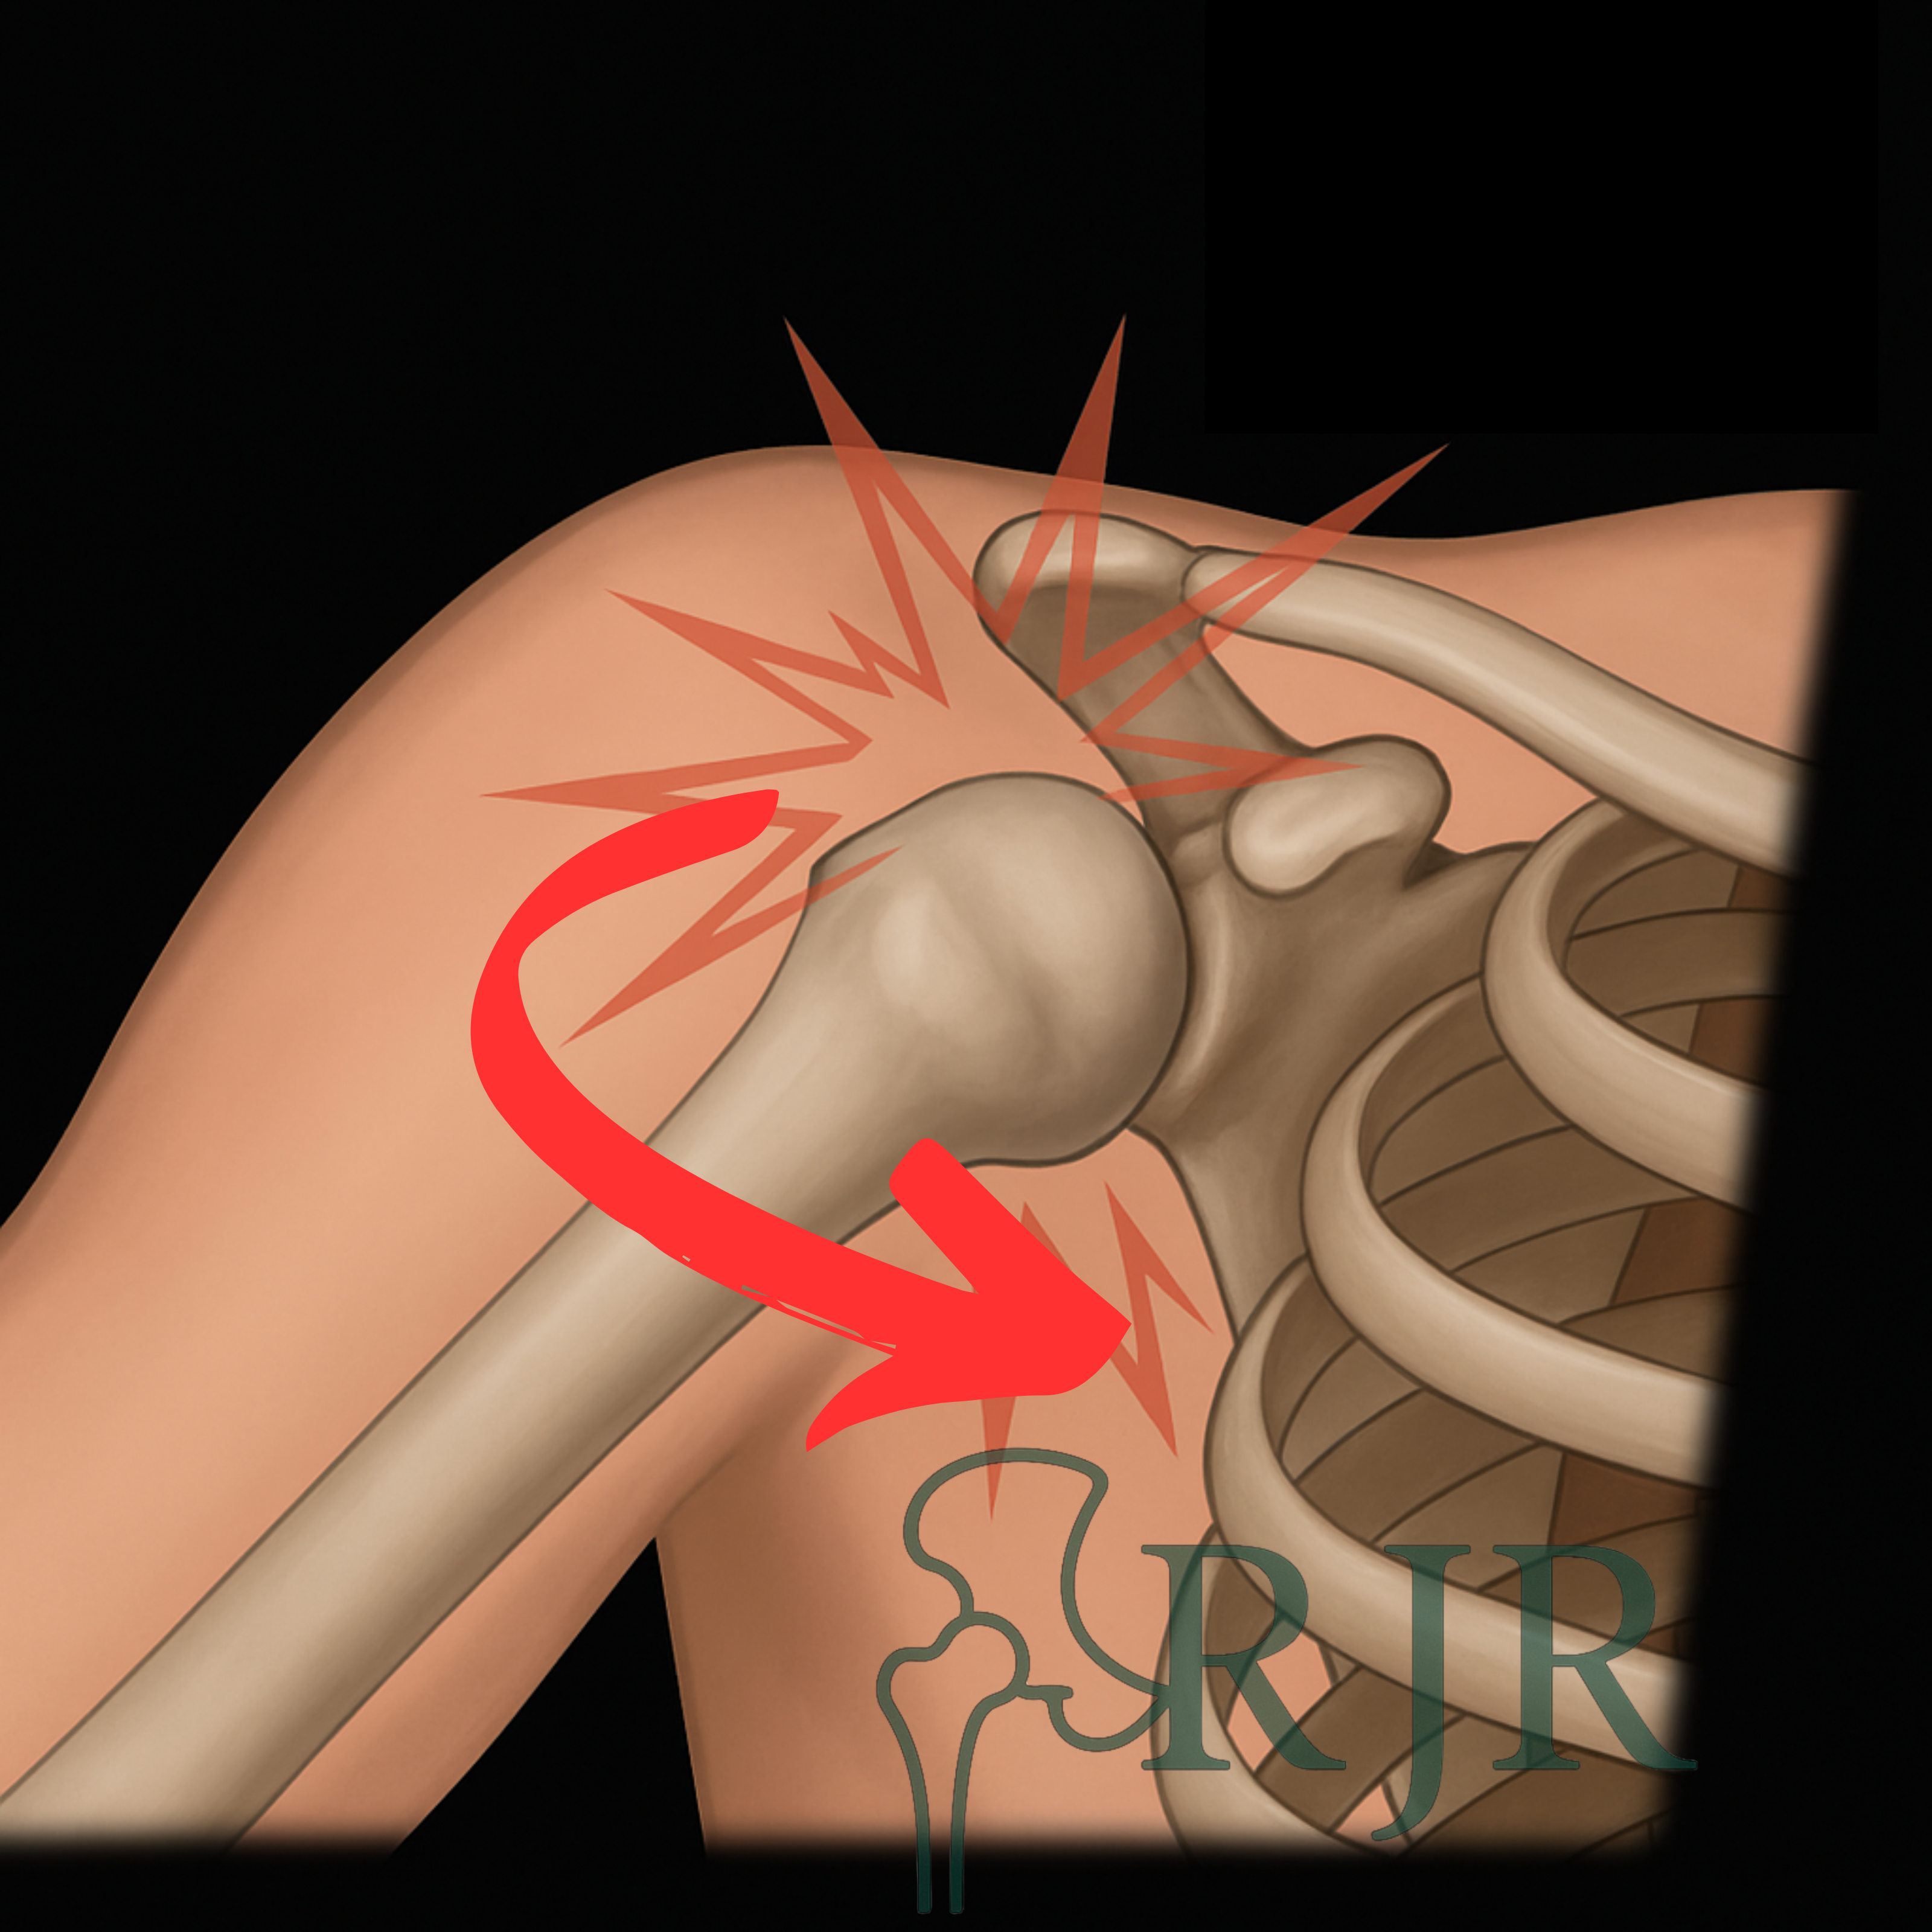

Luxações

Luxações ocorrem quando um osso sai do lugar na articulação, muitas vezes após traumas ou movimentos bruscos. O tratamento rápido e adequado é essencial para evitar complicações e garantir uma boa recuperação